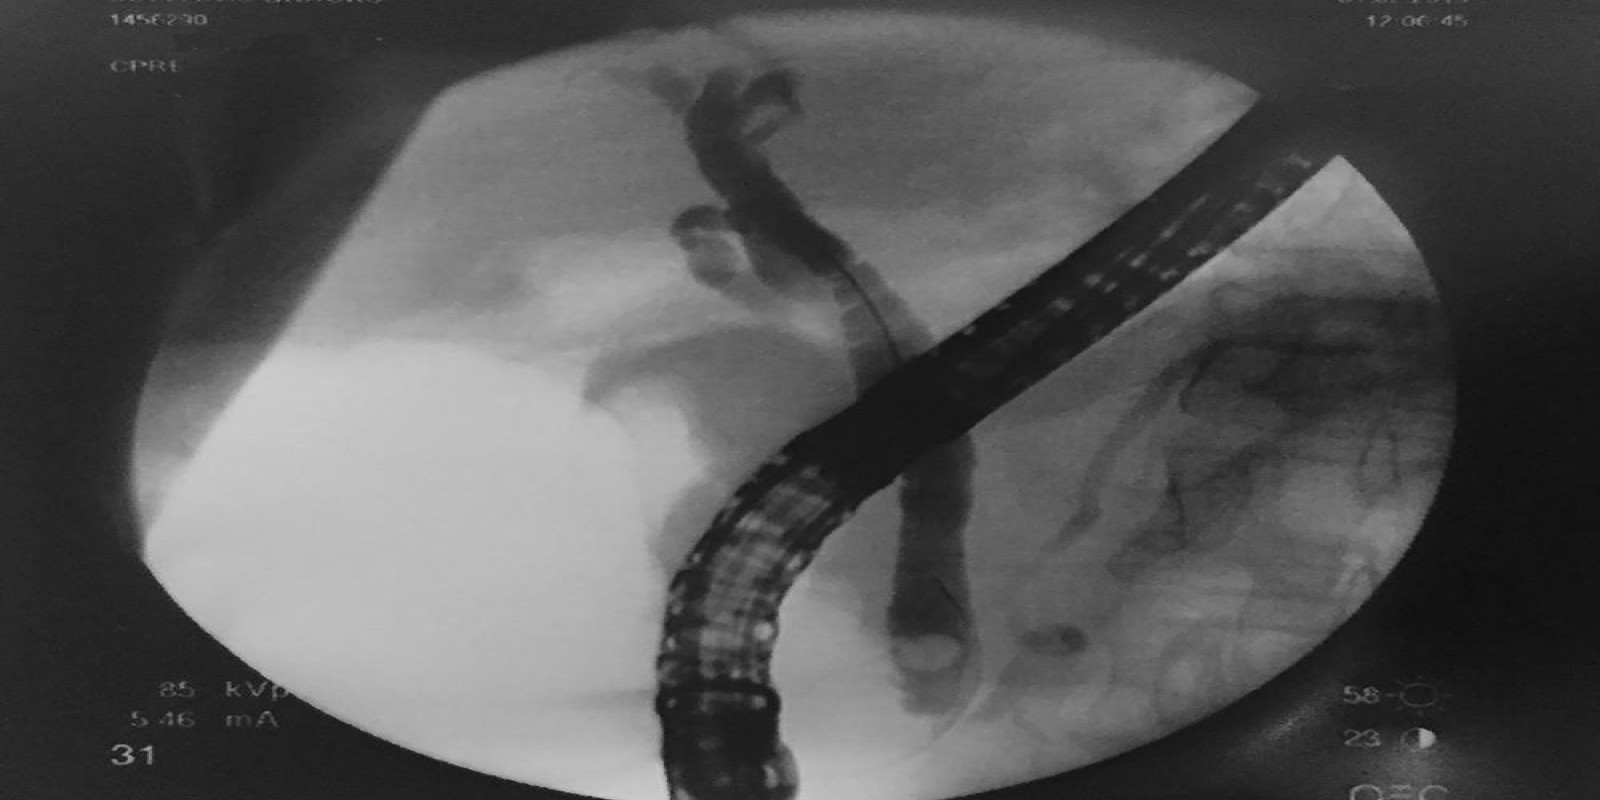

Caso Código 052A de Coledocolitíase

Cod.: 052A